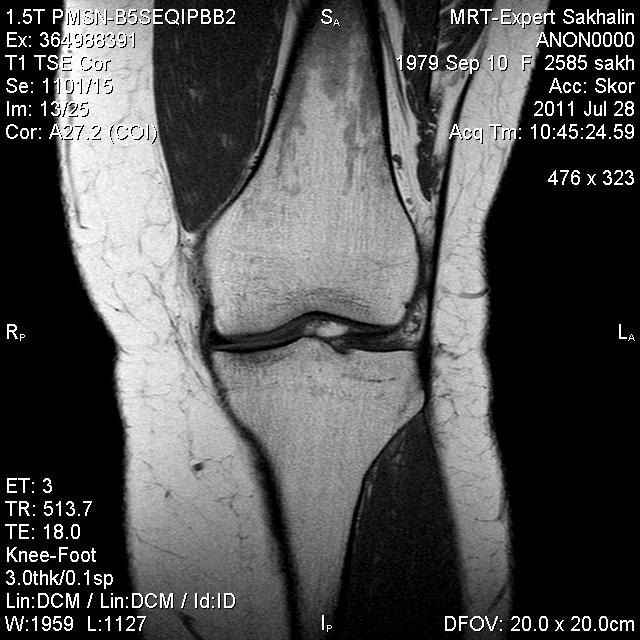

Коленный сустав

Подглядела случай у коллеги.

Что это может быть?

Не вижу криминала. А на что жалуется девушка?

P.S. В костях - это, скорее всего, резидуальный красный костный мозг.

Жалоба у всех одна на всех-болит.

участки гемопоэтического костного мозга